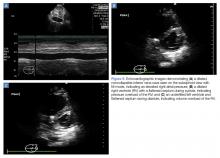

While inferior vena cava (IVC) ultrasound has been shown to be a pre-heart/lung assessment of cardiopulmonary interactions that predicts volume responsiveness, the IVC is also a good predictor of right atrial (RA) pressure. 35 If the IVC is dilated and lacks respiratory variation, the patient likely has an elevated RA pressure, which is most likely transmitted from an elevated RV pressure ( Figure 9a ). However, compliance of the RA, RA pressure and, by extension, IVC prediction of that RA pressure, may underestimate the degree of RV pressure or afterload.

Figure 9.

In the presence of pressure overload of the RV, septal motion will be toward the LV and flatten during systole ( Figure 9b ). Despite movement of the septum toward the LV on systole, the LV is still able to fill in diastole and maintain an adequate cardiac output (often with concomitant tachycardia). When the RV is volume-overloaded, the septum flattens on diastole, which has a more deleterious effect on cardiac output ( Figure 9c ). Due to pericardial restraint on the free wall of the LV, the LV is unable to fill during diastole and thus cardiac output drops. 30,36 The well-known “D-sign” occurs when the RV is both pressure- and volume-overloaded, which often occurs when a hypotensive patient with a pressure-overloaded RV receives a bolus of fluid. McConnell’s sign occurs when the pressure and volume-overloaded RV has apical “blinking” caused by tethering of the shared muscle fibers with the LV. 37